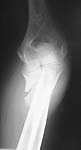

The olecranon is certainly comminuted, but if the wound is small all the pieces should be there. I would favor an attempt at ORIF w/ plating to reconstruct as much as possible. He is a young laborer and should have good bone quality.

The attached case was similar, but not quite as comminuted.

Injury: